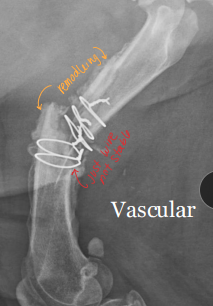

Remodeling Phase of Bone Fracture Healing

Step 3

Reorganization and reshaping of reparative tissue

Callus → more ordered structure and resorbed

↓ Cell density, ↓ vascularity = new bone formation

Matrix fibrils align along stress lines

Endochondral ossification → cartilage → bone

Woven bone → lamellar bone : late stages

Nonunion: No progression on rads for 3+ months, instability, poor blood supply

Vascular (viable): callus present, fracture line persists

Avascular (non-viable): little/no callus, poor biology